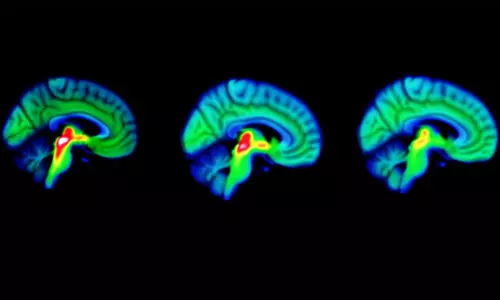

ലണ്ടൻ: പ്രമേഹം ചികിത്സിക്കാൻ പൊതുവെ ഡോക്ടർമാർ നിർദേശിക്കുന്ന മരുന്ന് പാർകിൻസൺസ്...